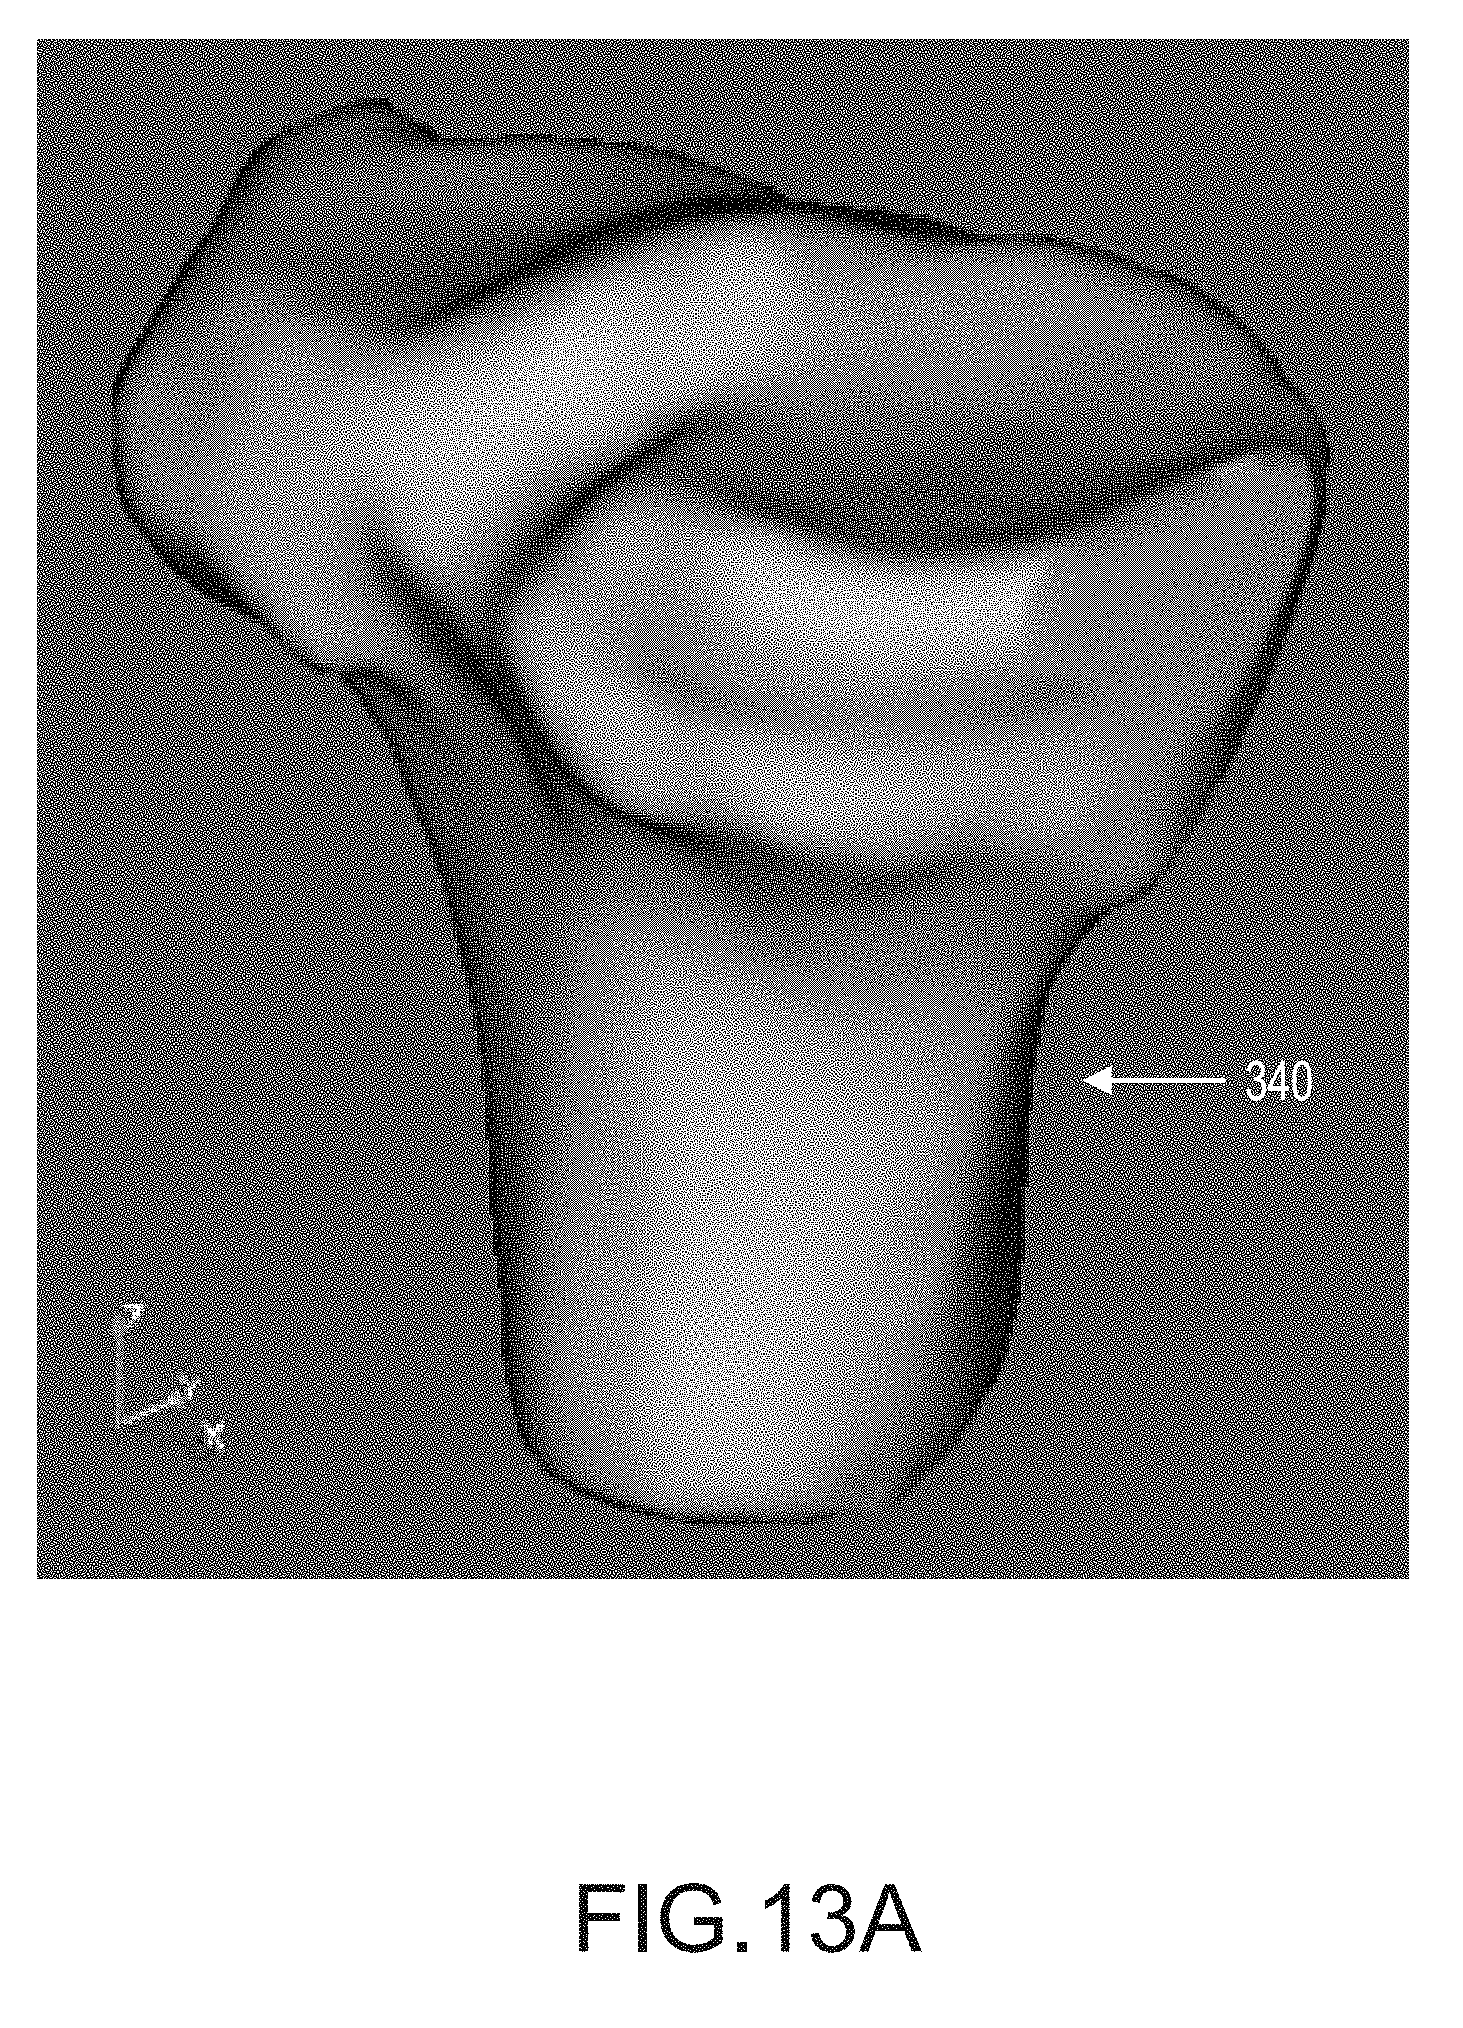

FIG. 13A depicts a golden tibia 3D mesh.

[0068]